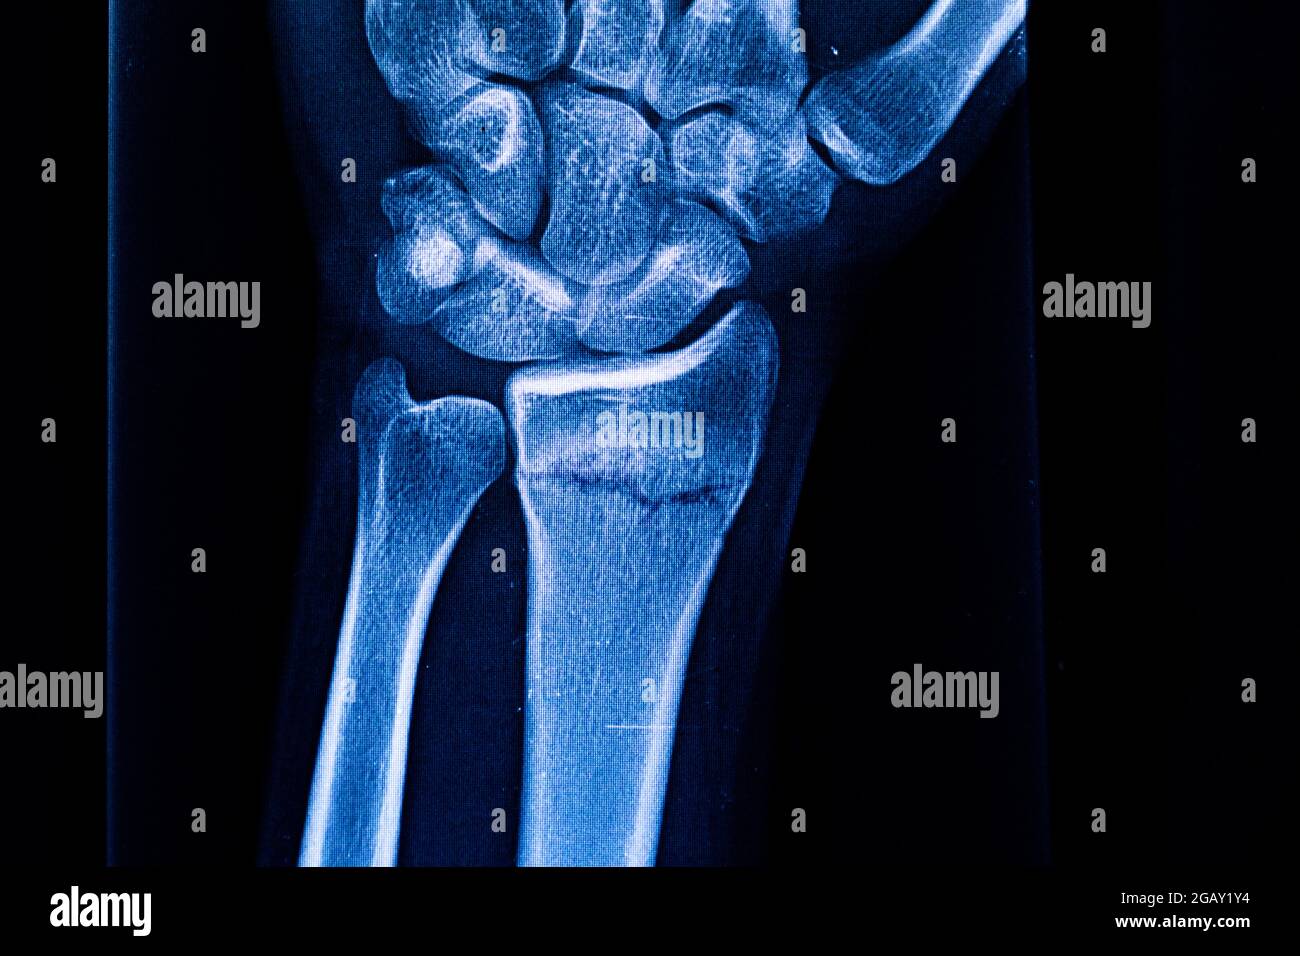

Xray image of Left wrist joint AP and Lateral view for showing Radius Bone Fracture X Ray What is a distal radius or wrist fracture? Radial head fractures can be subtle and easily missed on radiographs. They can also show how many pieces of broken bone there are. It is a break in one of the long forearm bones (radius) at your wrist, you can also break the ulna at the. It is important to assess the. Radius Bone Fracture X Ray.

Xray Image Right of Wrist Joint, Shows Fracture of the Distal Radius Radius Bone Fracture X Ray They can also show how many pieces of broken bone there are. In the elderly, osteoporotic fractures of the distal radius are common. It is a break in one of the long forearm bones (radius) at your wrist, you can also break the ulna at the. Radial head fractures can be subtle and easily missed on radiographs. In children, bone. Radius Bone Fracture X Ray.

Xray Image of Left Wrist Joint AP and Lateral View for Showing Radius Bone Fracture X Ray It is a break in one of the long forearm bones (radius) at your wrist, you can also break the ulna at the. What is a distal radius or wrist fracture? Radial head fractures can be subtle and easily missed on radiographs. The treatment decision of a distal radius fracture is complex and depends on the type of the fracture,. Radius Bone Fracture X Ray.